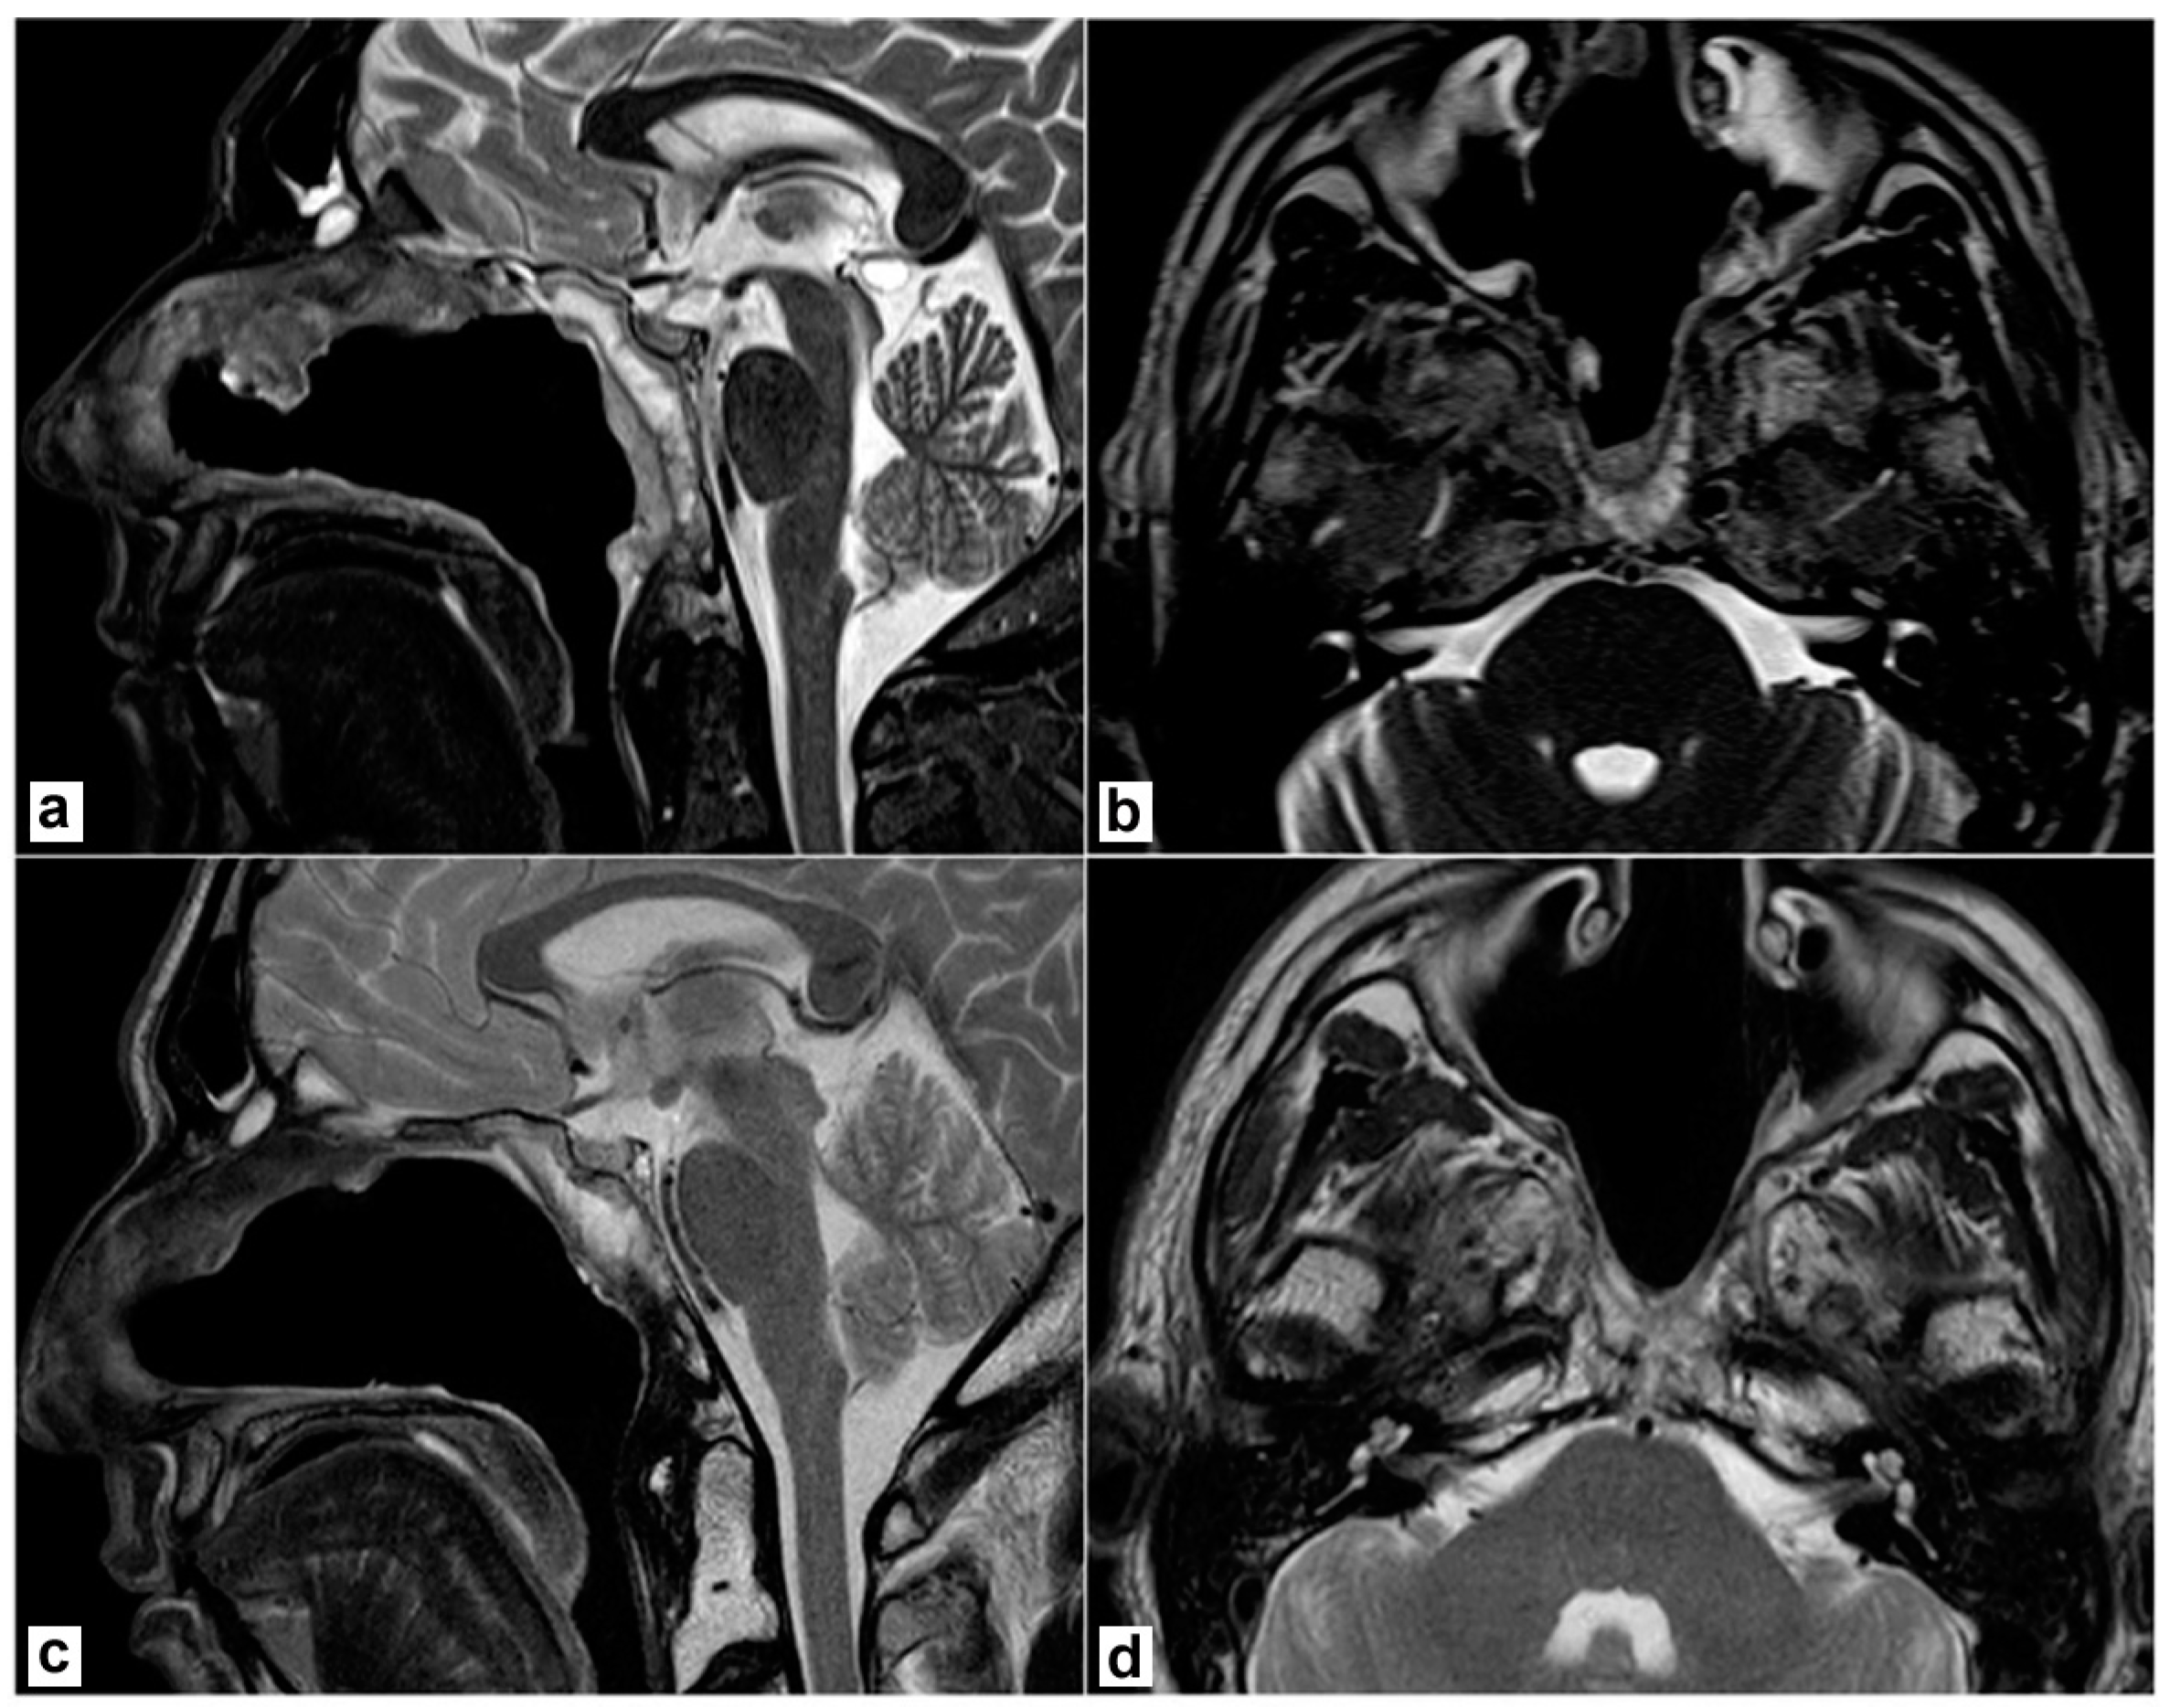

3.1. Case Presentation